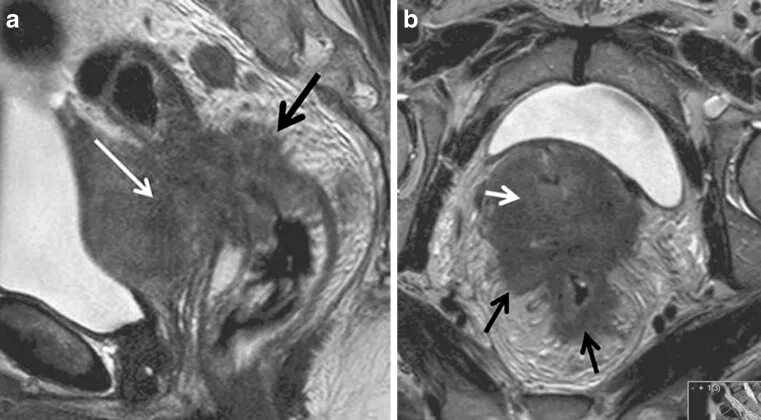

Метастазы в матке